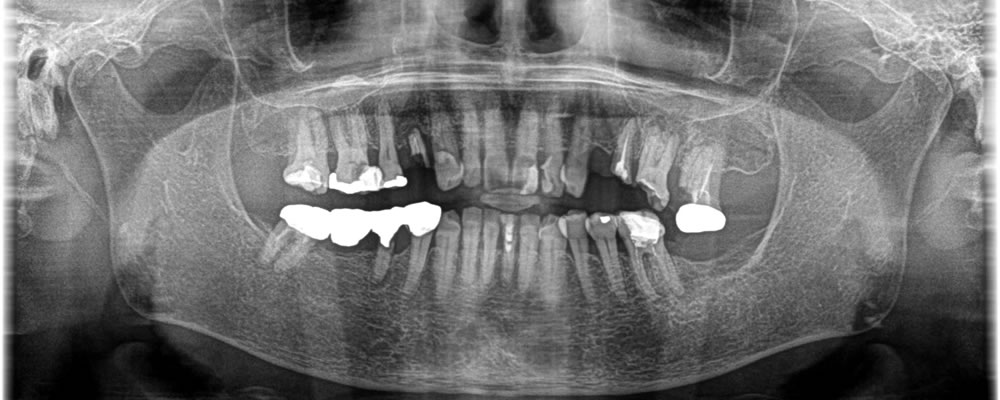

インプラント治療で抜歯した部分の咬み合わせを回復した症例

年齢

50代

性別

男性